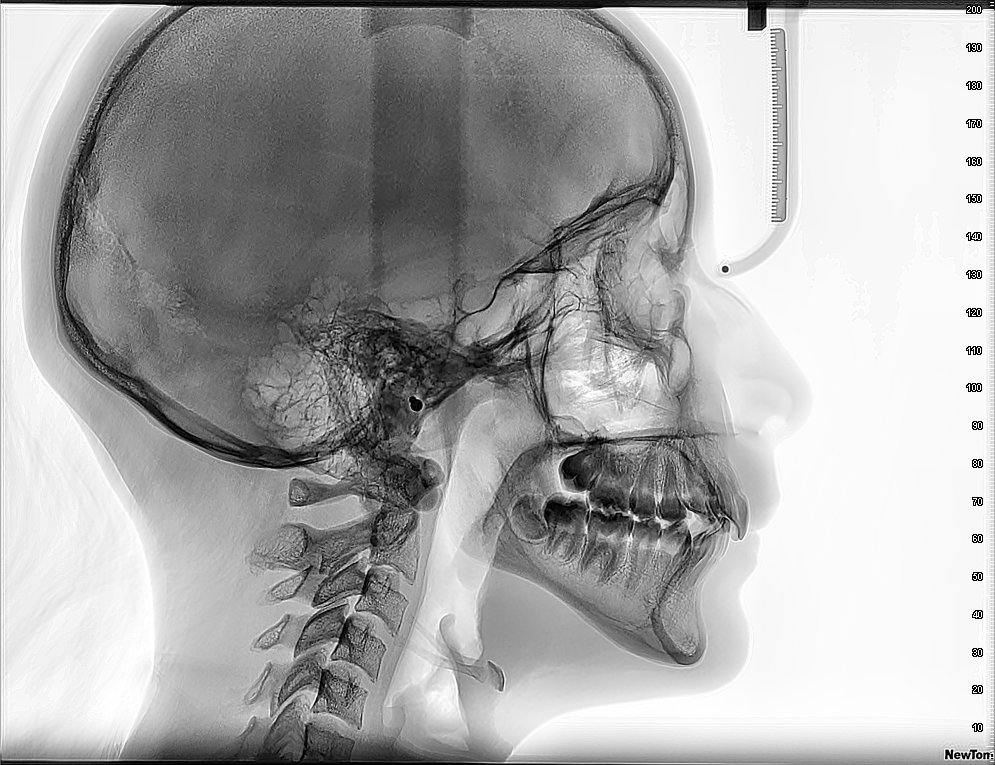

Un examen TAC cervical, también conocido como tomografía computarizada de la columna cervical, es una prueba de diagnóstico por imagen no invasiva. Utiliza un equipo especializado que emite haces de rayos X y un detector que gira alrededor del cuello, registrando la forma en que los tejidos absorben los rayos Un ordenador procesa esta información para crear imágenes transversales, o «rebanadas», de la región cervical. Estas imágenes se pueden reconstruir en 2D o 3D, ofreciendo una visión detallada de las vértebras, médula espinal, vasos sanguíneos y otros tejidos en el cuello. A diferencia de una radiografía convencional, que produce una imagen plana, un TAC proporciona una visión mucho más completa para identificar anomalías.

Un examen TAC cervical, también conocido como tomografía computarizada cervical, es una prueba de diagnóstico por imágenes que utiliza rayos X para crear imágenes detalladas de la región cervical, incluyendo la columna vertebral, los tejidos blandos y los vasos sanguíneos.